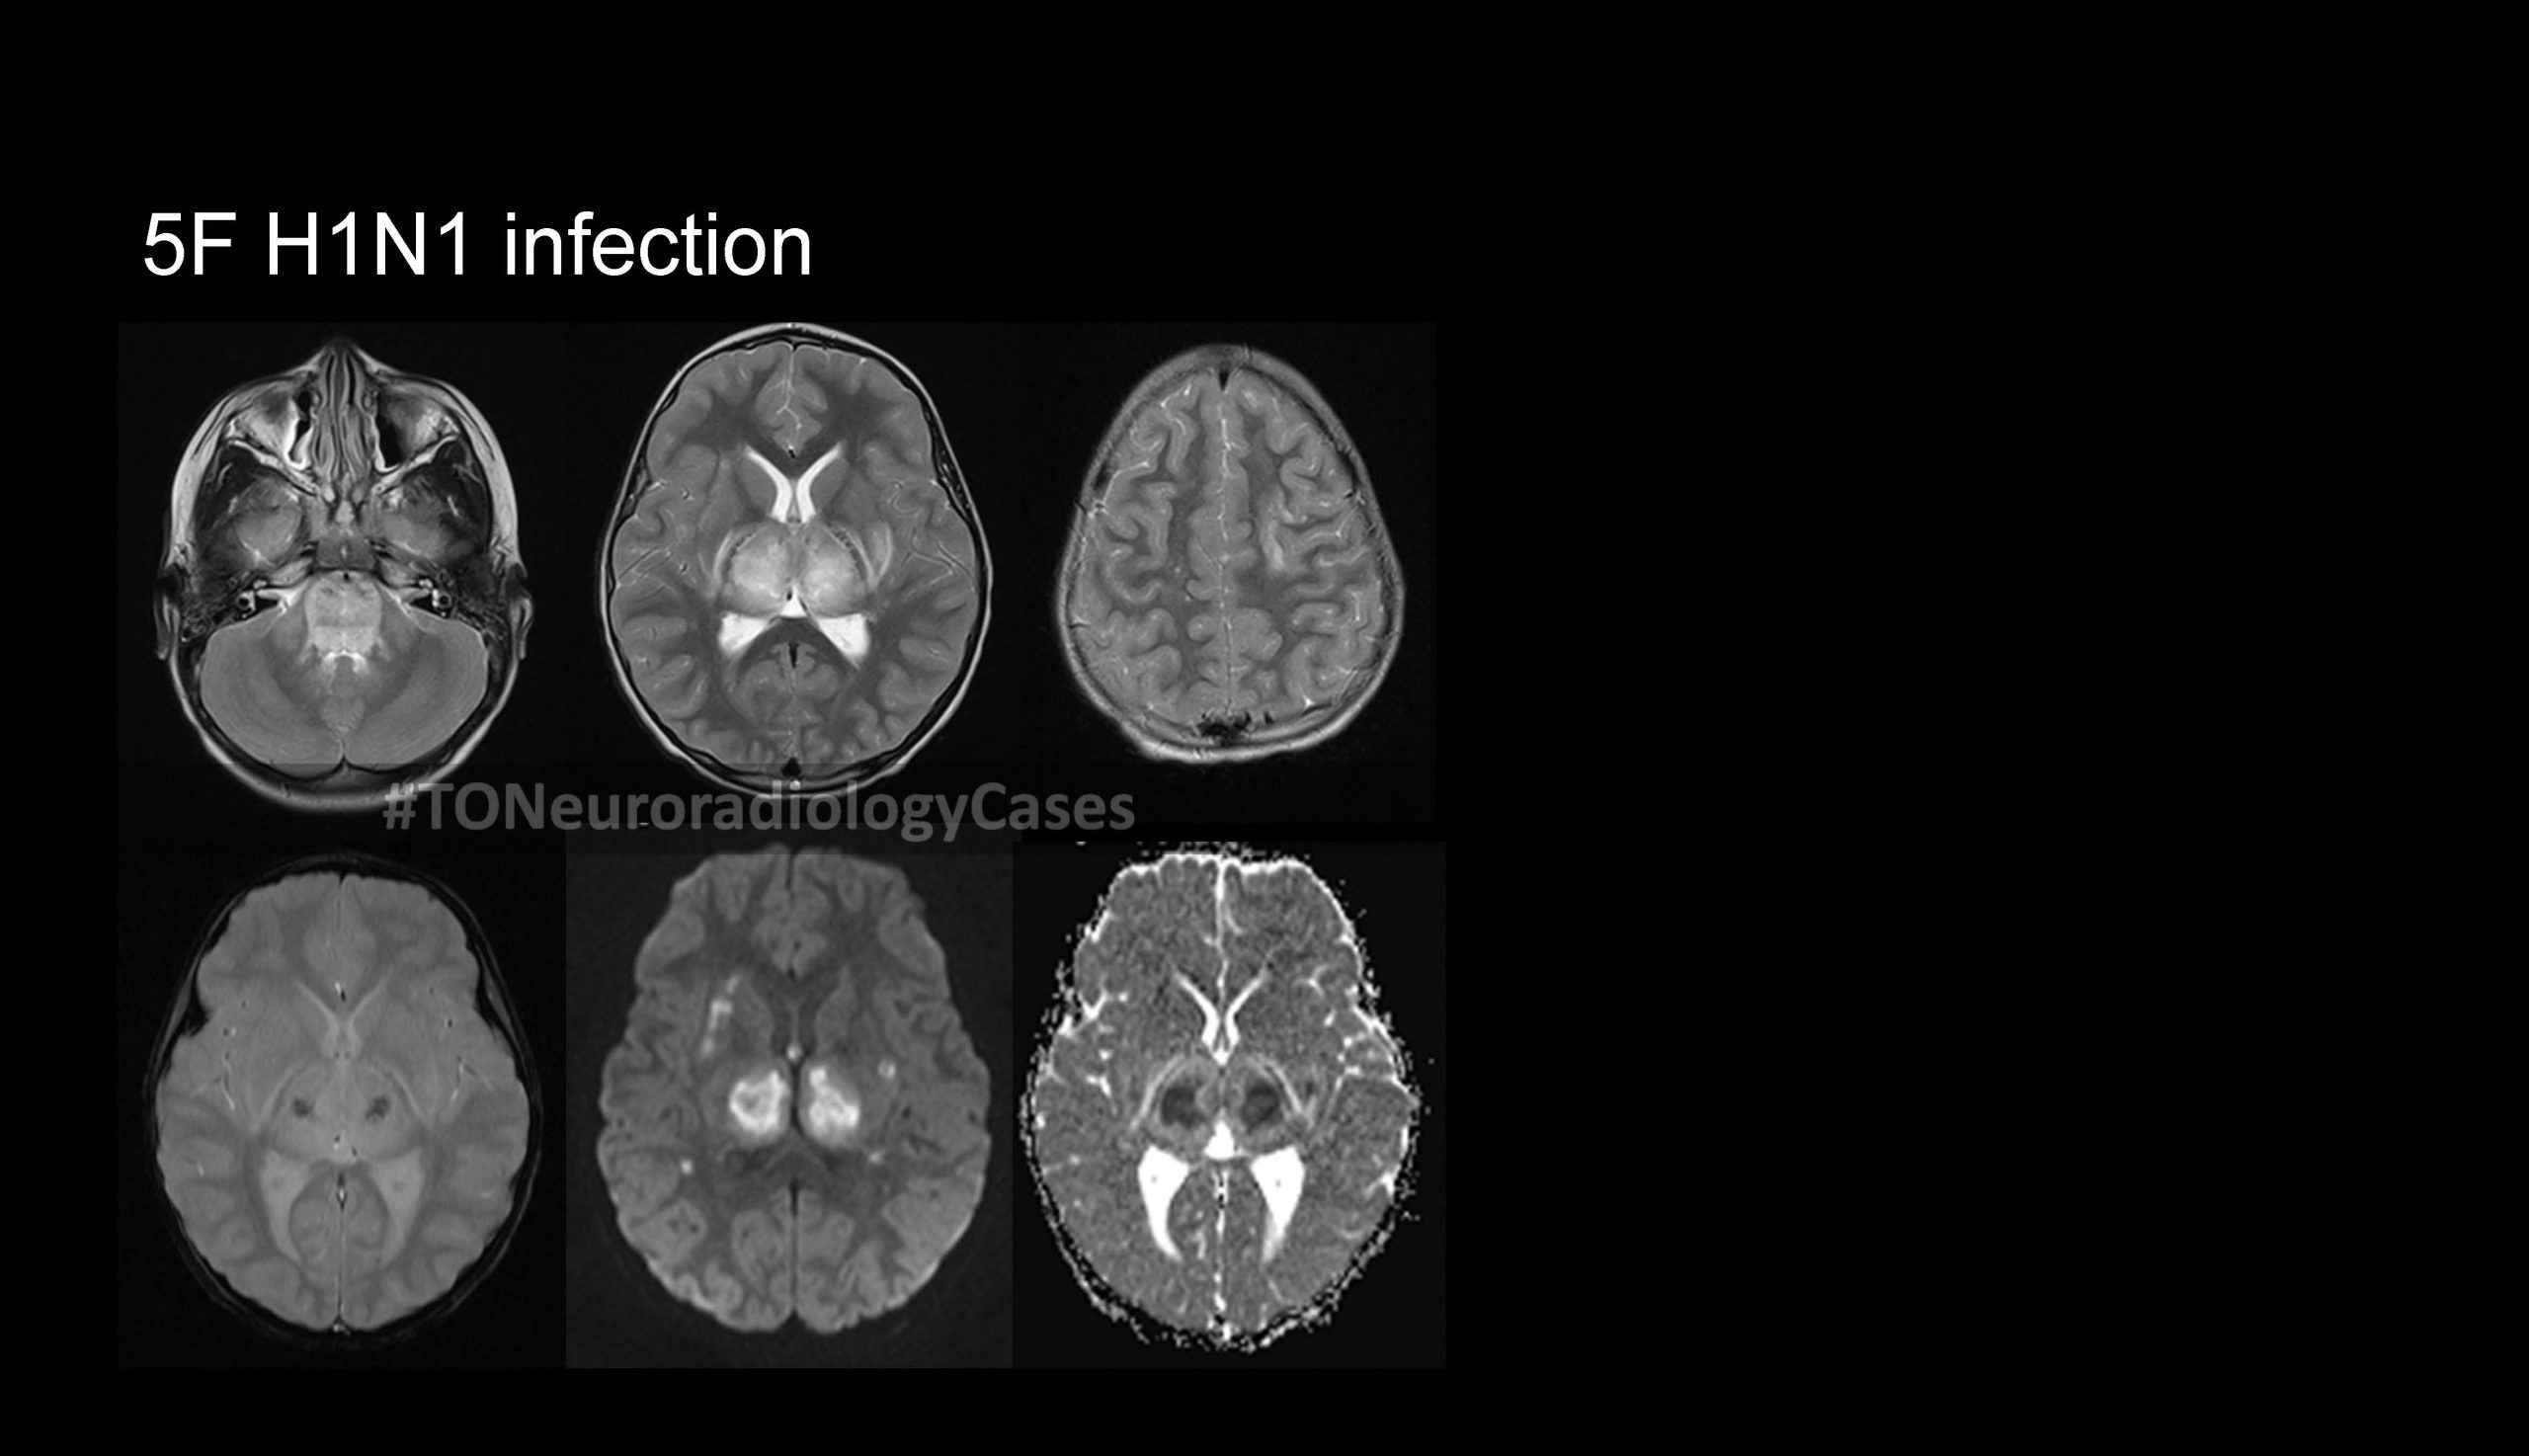

DR. AMY CHEN’S

Neuroradiology Case of the Week

@ Toronto Radiology

Over the past few years, I’ve had the pleasure of curating a “Case of the Week” contest with contributions from radiologists across the city, designed to challenge and engage our neuroradiology fellows at the University of Toronto. This collection showcases a range of neuroradiology cases from our city and have been a fun part of our fellow’s educational experience. I am excited to share this resource with a wider audience, now featured on our Toronto Radiology departmental website.

New cases will be added periodically, so be sure to check back for the latest updates!